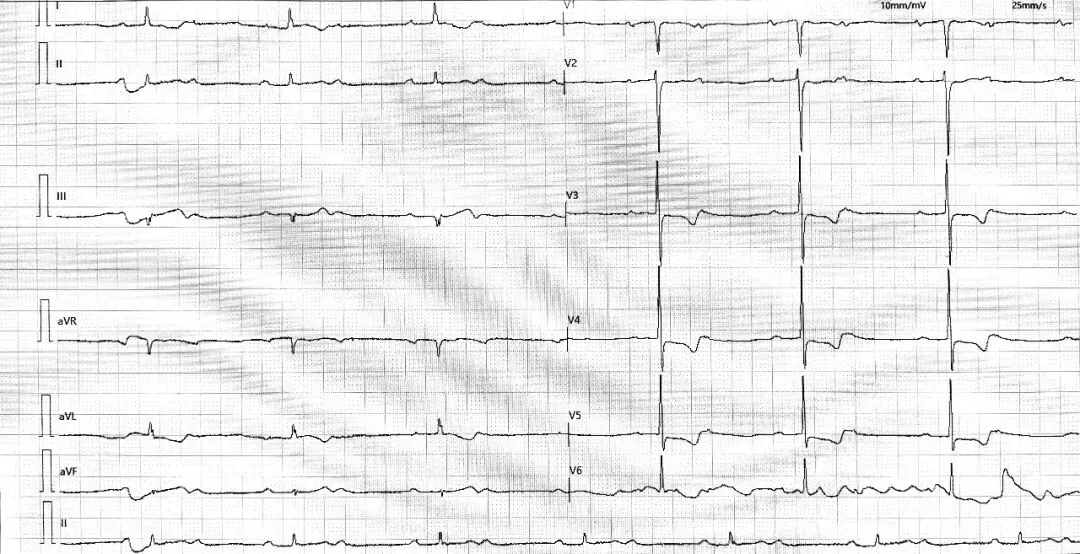

二度房室阻滞的诊断与分类依赖于对PR间期规律的测量判断

•PR间期进行性延长,直至一个P波后QRS波群脱落,形成一个长RR间期。

•脱落后的第一个PR间期恢复至最短,上述模式周而复始(文氏周期)。

•总体上呈现RR间期呈现“进行性缩短后突然延长”的特点,且长RR间期短于任何两个短RR间期之和。

•所有能够下传的P波,其PR间期恒定不变(可正常或延长)。

•QRS波群突然、不可预测地脱落,脱落前后的PR间期无变化。

•常伴宽QRS波群(束支阻滞图形)。